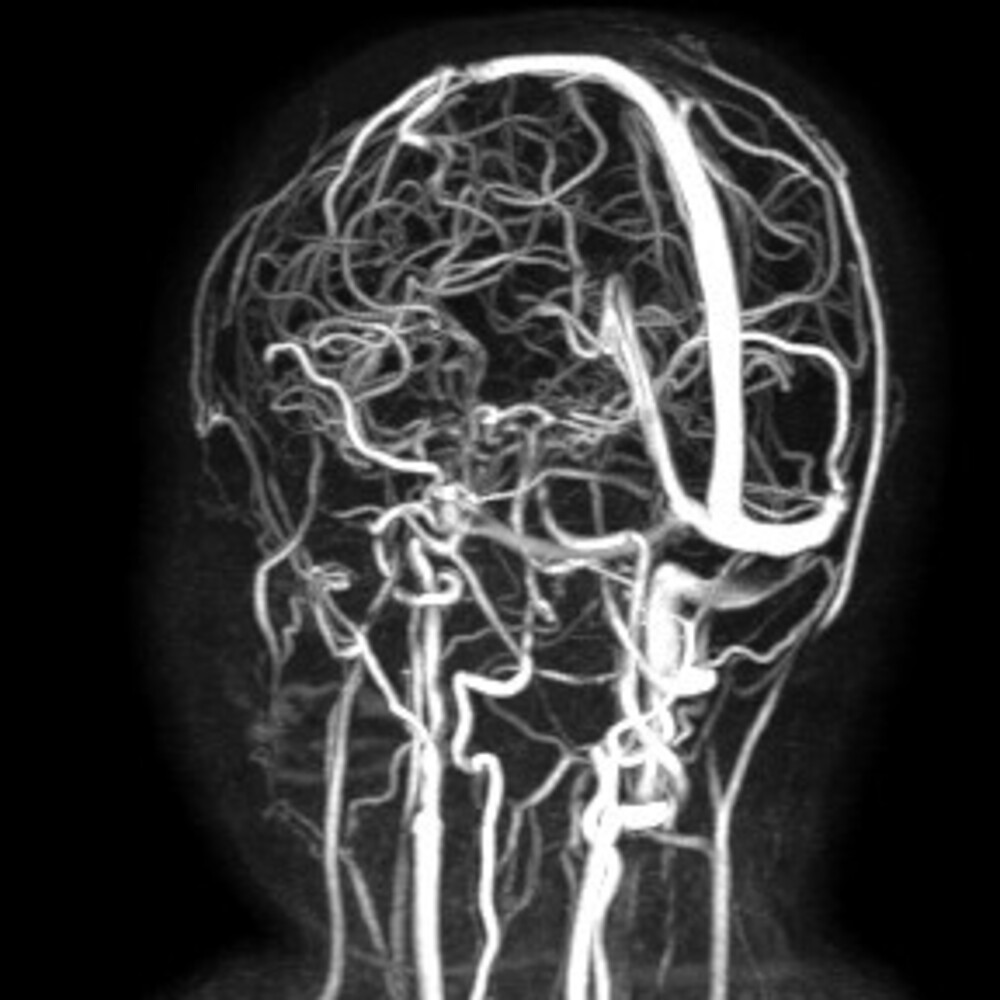

AGI - Ha recuperato completamente la vista una bambina di 10 anni sottoposta a un complesso percorso diagnostico e terapeutico frutto della collaborazione tra la Neurologia dell' ospedale Giovanni XXIII e le unità di Neurochirurgia e Otorinolaringoiatria del Policlinico di Bari. La piccola era giunta al Pronto soccorso pediatrico con un grave offuscamento visivo e una paralisi dei muscoli oculari . Gli accertamenti diagnostici avevano evidenziato una mastoidite dell'orecchio destro complicata da una trombosi venosa cerebrale , estesa fino al seno cavernoso, con un elevato rischio di perdita irreversibile della vista. E' stato immediatamente attivato un team multidisciplinare composto da neurologi pediatrici, neurochirurghi e otorinolaringoiatri, che ha deciso un intervento chirurgico combinato. L'equipe di Otorinolaringoiatria, diretta dal Nicola Quaranta, ha eseguito un drenaggio trans-timpanico per eliminare l'infezione all'origine della trombosi, mentre la Neurochirurgia, guidata dal Francesco Signorelli, ha effettuato una derivazione spinale esterna per ridurre indirettamente la pressione intracranica e la compressione sui nervi ottici. La tecnica utilizzata "Un approccio delicato, mini-invasivo e mirato - spiega Signorelli - che ci ha permesso di salvare la vista della bambina evitando l'impianto di protesi definitive. In età pediatrica questo è un aspetto fondamentale, perchè una protesi avrebbe richiesto nel tempo ulteriori interventi". Il protocollo condiviso di trattamento dell'ipertensione intracranica cronica ha consentito, nei 20 giorni successivi all'intervento, una progressiva riduzione delle pressioni intracraniche e la completa regressione del deficit di motilità oculare. Dopo tre settimane la derivazione è stata rimossa e la bambina è stata dimessa. Al controllo a sei mesi la trombosi risultava quasi del tutto risolta e la vista completamente recuperata, senza deficit residui. "Nel 2025 - conclude il direttore generale del Policlinico di Bari, Antonio Sanguedolce - sono state eseguite oltre 70 procedure neurochirurgiche pediatriche, circa la metà per tumori cerebrali . Risultati come questo dimostrano l'efficacia del modello multidisciplinare, capace di offrire anche ai pazienti più piccoli cure sicure e avanzate".